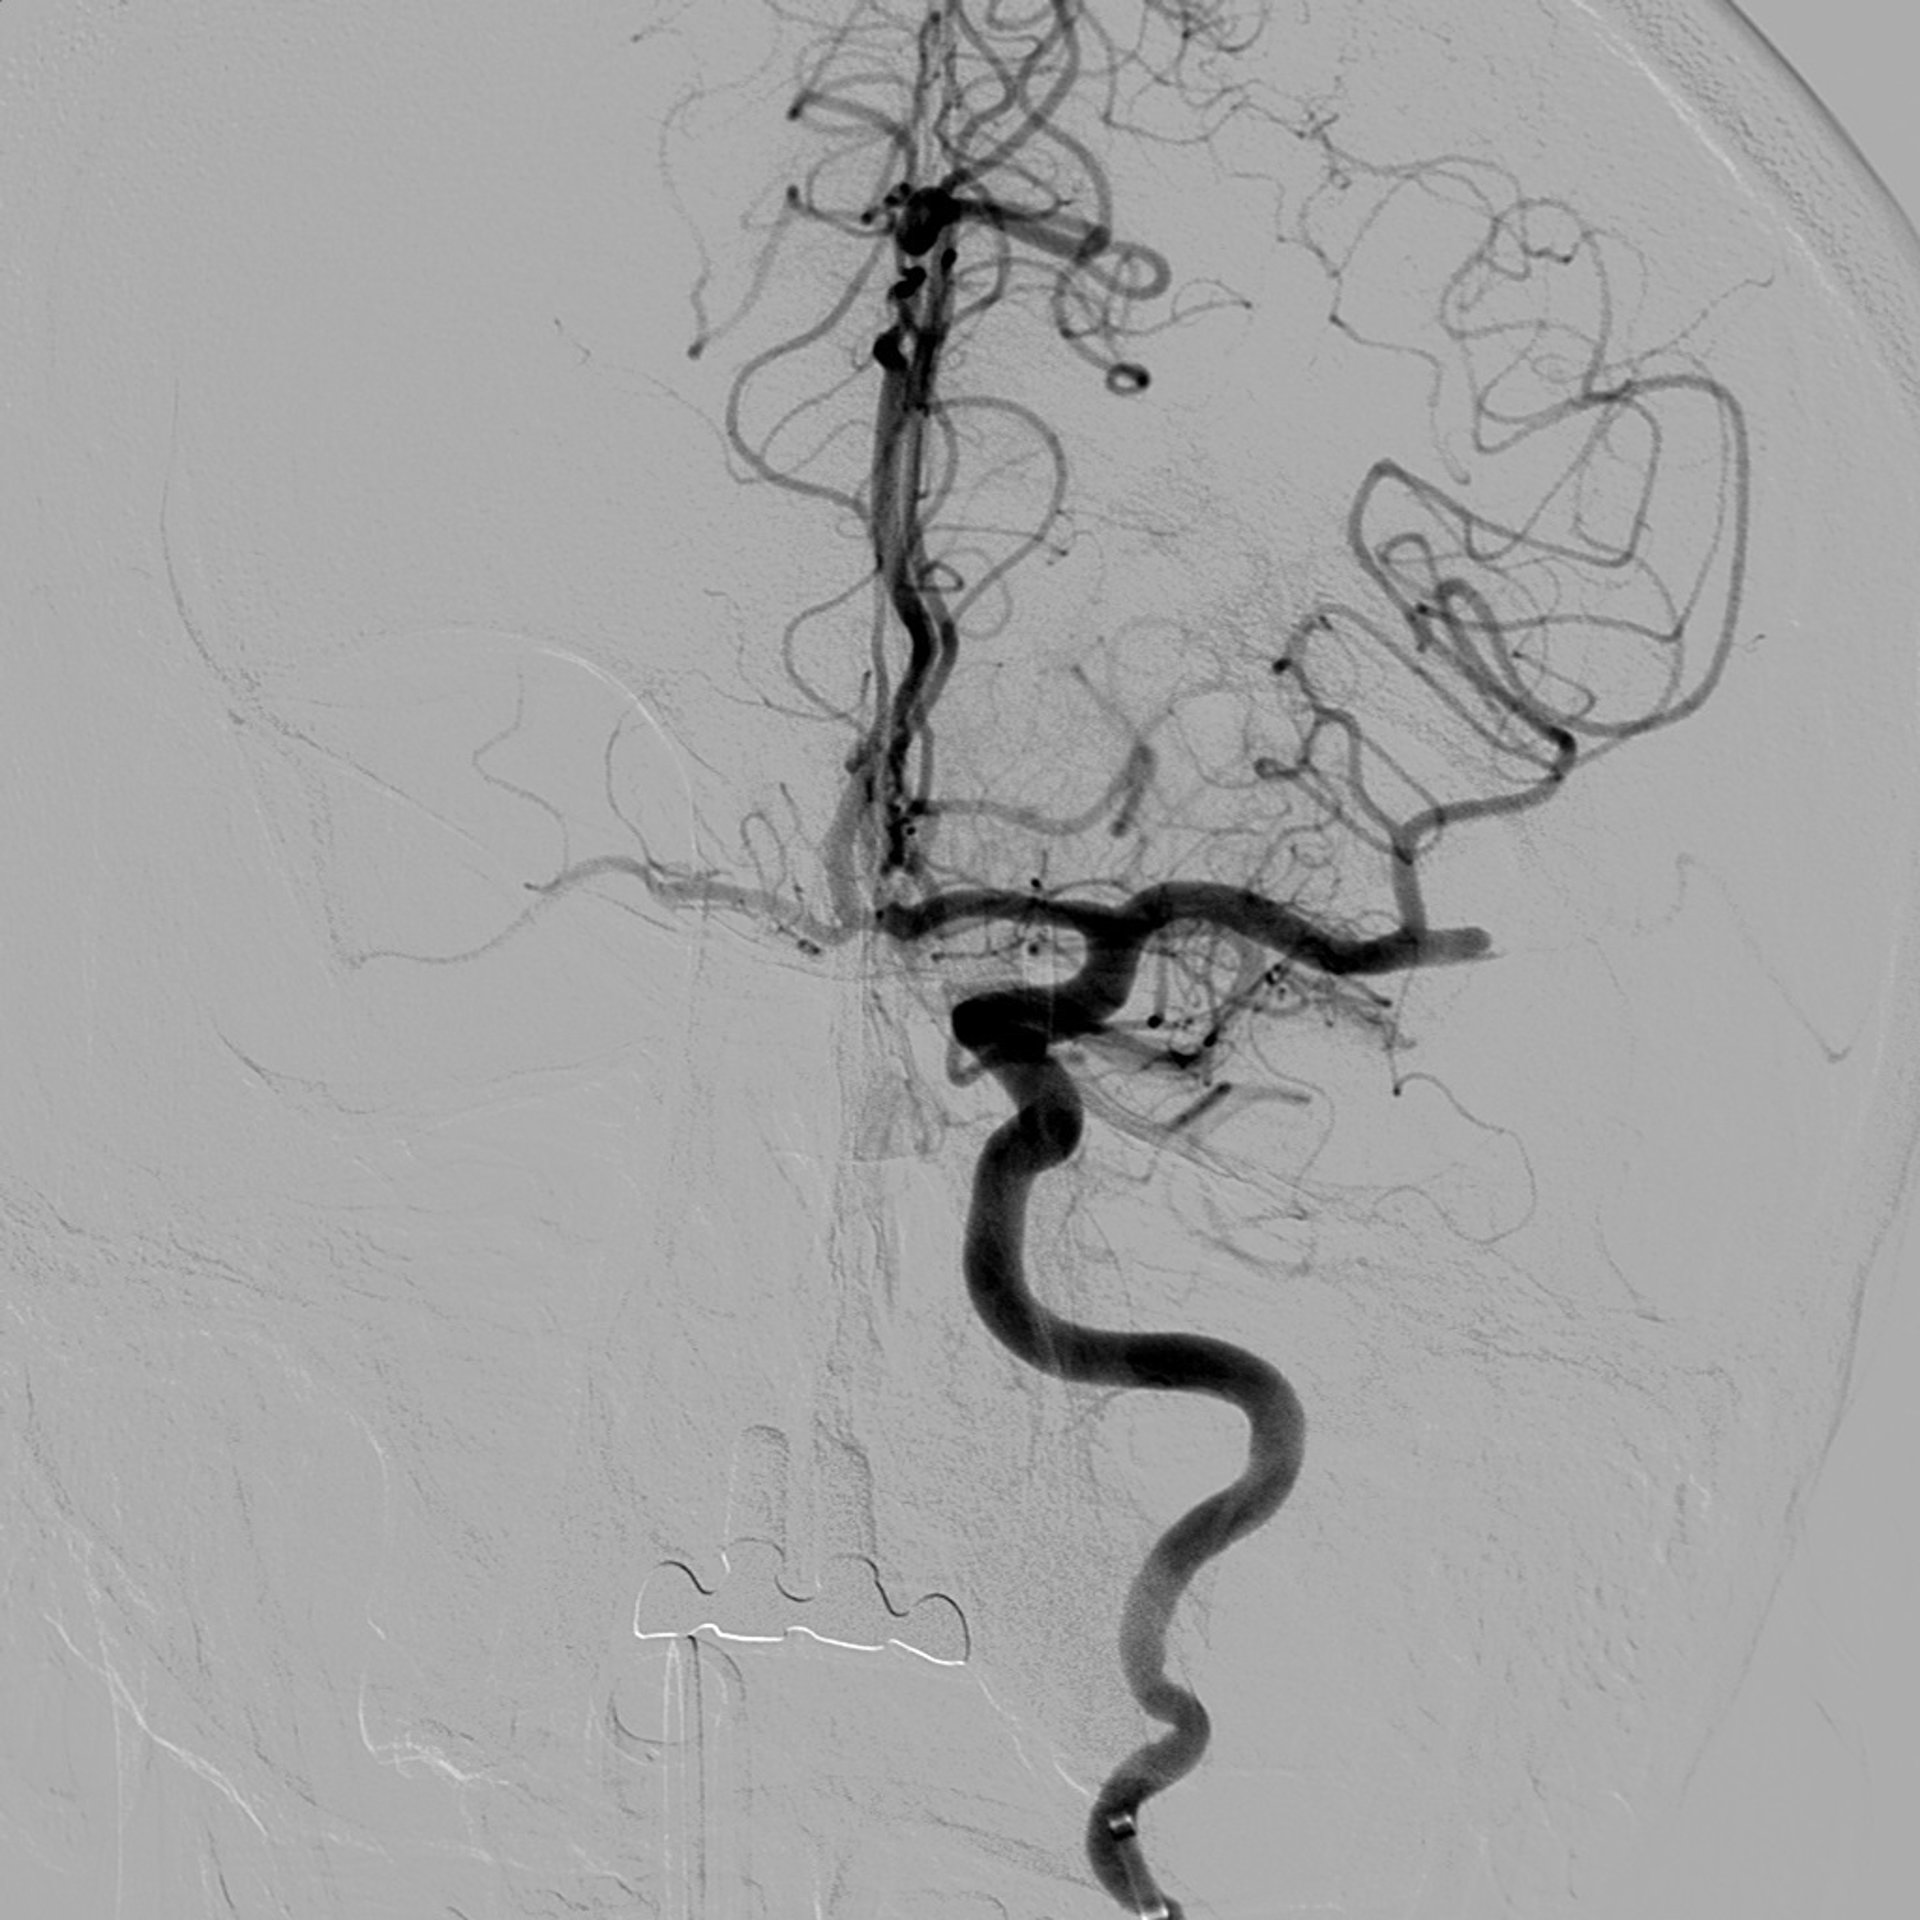

Imagen de arteria obstruida con trombo

CEDIDA